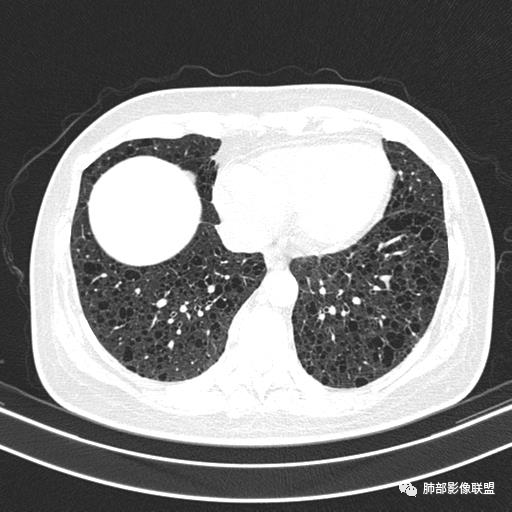

中年女性,不吸烟

双肺弥漫囊腔,累及肋膈角,囊腔形态相对规则单一。

符合LAM

CT平扫示双肺弥漫分布大小不等囊状薄壁透光区,无内、中、外带分布差异,间质稍示增厚。拟LAM

中年女性育龄期妇女,咳嗽气喘,无吸烟史,有苯吸入史。影像:双肺弥漫均匀小囊腔,无明显分布优势,囊腔形态欠规则,壁薄,部分囊腔边缘血管征,伴双肺弥漫磨玻璃影,无结节,考虑lam,鉴别苯中毒肺损伤,囊腔多有分布优势,小叶中心分布为主,形态规整等

中年女性,两肺弥漫分布囊性低密度影,壁薄,相对规则,境界尚清晰,考虑LAM

中年育龄期女性,双肺多发含气囊腔弥漫性分布,囊间肺组织结构正常,常规考虑Lam

女,46,活动性气喘1年。苯吸入史半年。胸部CT:两肺弥漫囊腔,上至肺尖,下至肋膈角,形态类似小囊腔。考虑:LAM,鉴别LIP,BHD,PLCH等。

双肺弥漫大小不一薄壁含气囊腔,囊间肺组织正常,正常肺背景,肺尖肺底受累;青年女性,气喘,支持LAM

双肺多发大小相近的囊状影,分布趋势趋于一致,中年女性,考虑LAM。部分囊内见血管及分隔影,小叶中心性肺气肿代排

CT表现:双肺弥漫大小不等的薄壁囊腔,囊壁<2mm,外形规则,血管影多位于囊腔周围,囊腔之间肺组织正常,随着疾病进展到晚期,囊腔变大、增多,不可胜数,囊腔可融合成较大的囊,与肺气肿相似,形成间质性肺纤维化。部分病例可出现结节影。